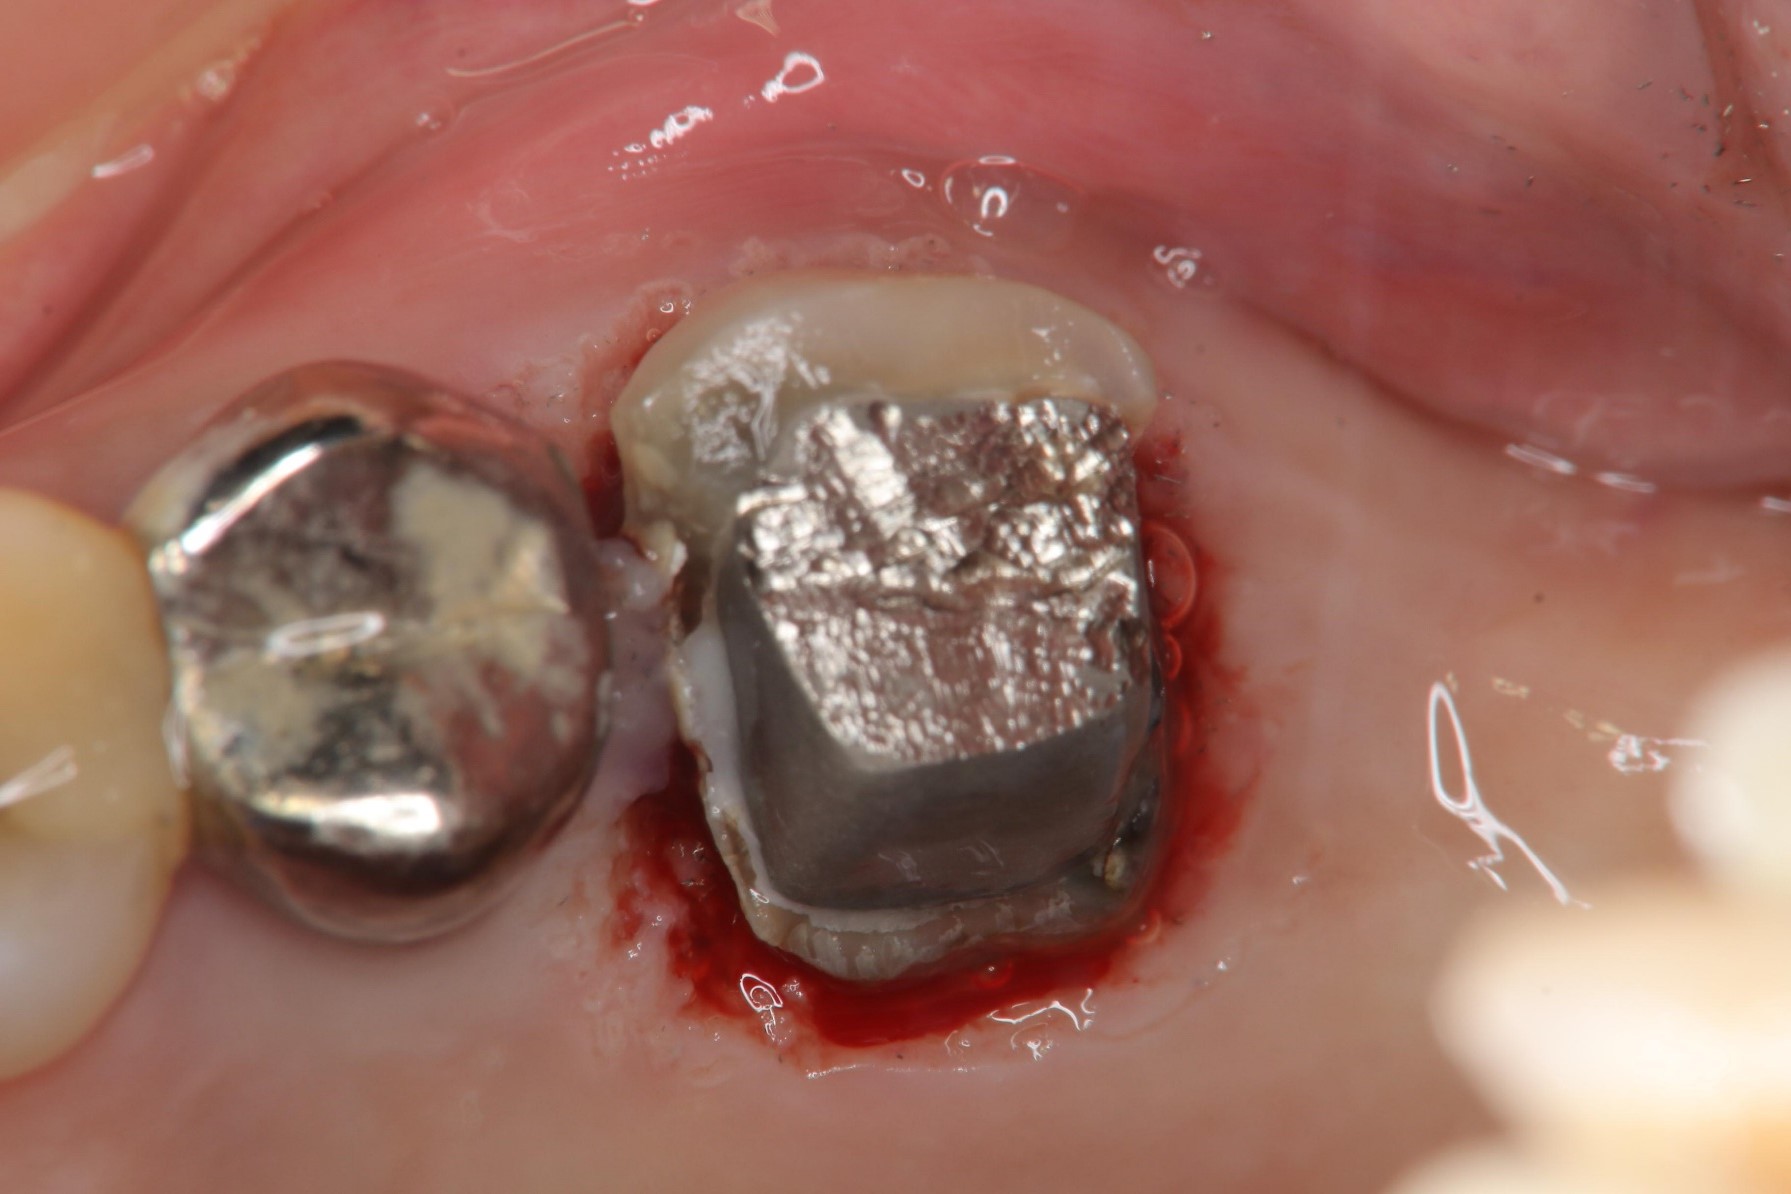

水雷射牙冠增長手術